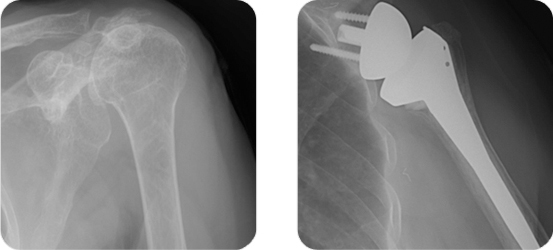

환자의 나이, 직업, 필요한 기능 정도, 파열의 크기, 기능 저하의 정도, 손상 기전, 통증의 정도 등을 감안하여 결정합니다. 먼저 힘줄의 파열이 부분적으로 있는 경우에는 비수술적 치료를 먼저 시행합니다. 비수술적 치료법으로는 약물 또는 주사를 이용한 통증 치료, 스트레칭을 이용한 관절운동, 어깨 주위 근력 강화 운동 등이 있으며 파열이 심하지 않거나 75세 이상의 고령 환자에게 시행합니다. 반면 힘줄의 전체두께가 파열된 전층 파열의 경우 일반적으로 수술적 치료를 시행합니다. 또한 활동이 많을 것으로 예상되는 젊은 연령의 환자, 강한 외력에 의한 외상성 파열이라고 진단되는 경우, 심각한 기능 이상 및 근력의 저하를 동반한 경우 등에서도 수술을 고려하는 것이 일반적입니다. 수술적 치료는 파열된 힘줄의 봉합하는 것이 기본이며 통증이 원인이 되는 점액낭염, 활액막염 등을 제거하고 힘줄과 충동을 일으킬 수 있는 견봉이나 오구돌기 같은 뼈들의 일부를 제거하는 것이 주 내용입니다. 과거 개방적 술식으로 봉합을 하였으나 현재는 관절경을 이용한 봉합술이 널리 사용되고 있습니다. 파열의 크기가 광범위하고 끊어진 파열 부위가 몸쪽으로 들어간 퇴축이 아주 심할 경우는 봉합이 불가능하거나 봉합해도 다시 재파열 될 확률이 높습니다. 이와 같은 경우, 노인에게는 심한 통증과 근력 약화로 일생생활에 장애가 심하다면 역 견관절 전 치환술이라는 인공 관절 수술을 시행할 수 있습니다. ![]() 회전근 파열이 심해져 관절염이 생기거나 팔을 전혀 들어 올릴 수 없는 마비 증상이 왔을 때 역 견관절 치환술을 시행합니다. ![]() |